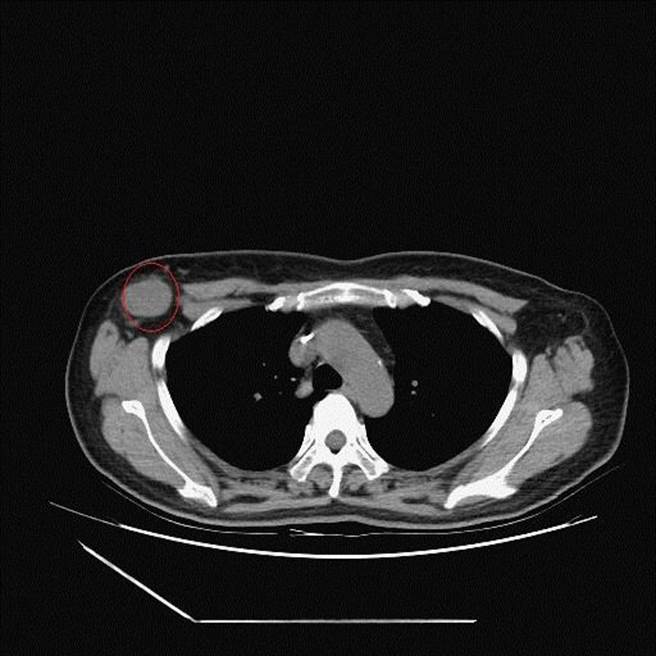

李忠懷表示,經乳房超音波、粗針切片及電腦斷層檢查,證實個案為第三期的乳癌併發腋下淋巴結轉移,乳房腫瘤5公分、淋巴結腫瘤3.2公分,推估腫瘤已存在數月,並非打疫苗引起;目前正透過化療將腫瘤縮小後,再手術切除。

他強調,若為惡性腫瘤轉移,淋巴結皮質會增厚,透過超音波檢查就能看得出來;因此提醒民眾,若施打疫苗後不只是淋巴結腫大,還有身體其他地方也出現腫塊,務必盡快就醫檢查,確認是否為血栓引起,或是有其他病因。